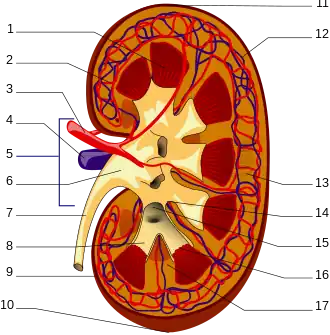

Structure

In humans, the kidneys are located high in the abdominal cavity, one on each side of the spine, and lie in a retroperitoneal position at a slightly oblique angle.[9] The asymmetry within the abdominal cavity, caused by the position of the liver, typically results in the right kidney being slightly lower and smaller than the left, and being placed slightly more to the middle than the left kidney.[10][11][12] The left kidney is approximately at the vertebral level T12 to L3,[13] and the right is slightly lower. The right kidney sits just below the diaphragm and posterior to the liver. The left kidney sits below the diaphragm and posterior to the spleen. On top of each kidney is an adrenal gland. The upper parts of the kidneys are partially protected by the 11th and 12th ribs. Each kidney, with its adrenal gland is surrounded by two layers of fat: the perirenal fat present between renal fascia and renal capsule and pararenal fat superior to the renal fascia.

The human kidney is a bean-shaped structure with a convex and a concave border.[14] A recessed area on the concave border is the renal hilum, where the renal artery enters the kidney and the renal vein and ureter leave. The kidney is surrounded by tough fibrous tissue, the renal capsule, which is itself surrounded by perirenal fat, renal fascia, and pararenal fat. The anterior (front) surface of these tissues is the peritoneum, while the posterior (rear) surface is the transversalis fascia.

The functional substance, or parenchyma, of the human kidney is divided into two major structures: the outer renal cortex and the inner renal medulla. Grossly, these structures take the shape of eight to 18 cone-shaped renal lobes, each containing renal cortex surrounding a portion of medulla called a renal pyramid.[18] Between the renal pyramids are projections of cortex called renal columns.

The tip, or papilla, of each pyramid empties urine into a minor calyx; minor calyces empty into major calyces, and major calyces empty into the renal pelvis. This becomes the ureter. At the hilum, the ureter and renal vein exit the kidney and the renal artery enters. Hilar fat and lymphatic tissue with lymph nodes surround these structures. The hilar fat is contiguous with a fat-filled cavity called the renal sinus. The renal sinus collectively contains the renal pelvis and calyces and separates these structures from the renal medullary tissue.[19]

Blood supply

The kidneys receive blood from the renal arteries, left and right, which branch directly from the abdominal aorta. The kidneys receive approximately 20–25% of cardiac output in adult human.[18][20][21] Each renal artery branches into segmental arteries, dividing further into interlobar arteries, which penetrate the renal capsule and extend through the renal columns between the renal pyramids. The interlobar arteries then supply blood to the arcuate arteries that run through the boundary of the cortex and the medulla. Each arcuate artery supplies several interlobular arteries that feed into the afferent arterioles that supply the glomeruli.

Blood drains from the kidneys, ultimately into the inferior vena cava. After filtration occurs, the blood moves through a small network of small veins (venules) that converge into interlobular veins. As with the arteriole distribution, the veins follow the same pattern: the interlobular provide blood to the arcuate veins then back to the interlobar veins, which come to form the renal veins which exit the kidney.